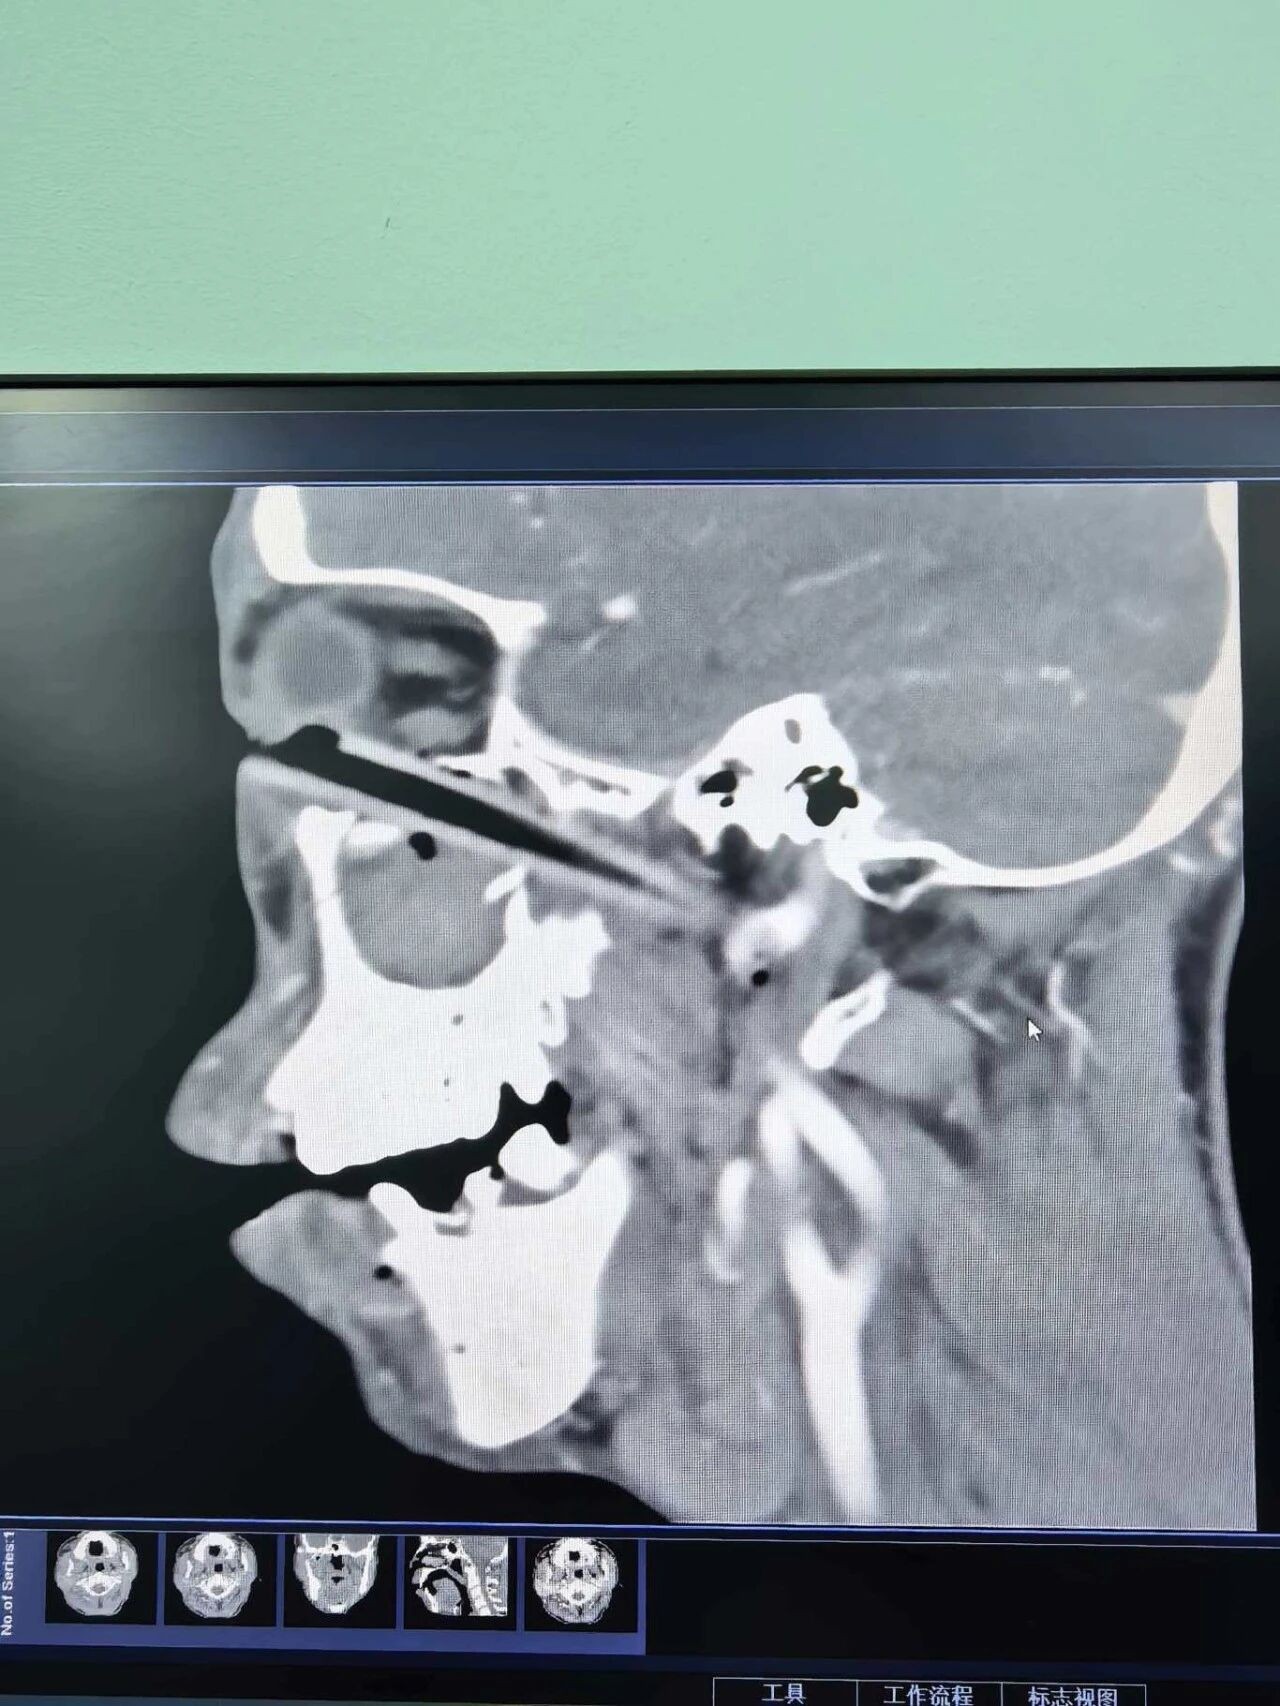

2月23日,55岁患者因干农活摔倒致“树枝”刺入右眼,由当地医院转入。入院时右眼肿胀、眼球固定,视力仅存眼前指数1米。CT显示:一根木质异物从右眼内眦部穿入,经眼眶、上颌窦、前颅底直达颈旁,尖端紧贴右侧颈总动脉。

入院检查令人倒吸一口凉气:CT显示,一巨大异物从右眼内眦部刺入,不仅穿透眼眶底壁进入上颌窦,还接连“凿穿”上颌窦前后壁,闯入翼腭窝,进而穿透前颅底,轨迹直抵右侧颈部,尖端竟与颈总动脉管壁紧贴。

CT显示,右侧眼眶被异物贯穿,并穿透右侧鼻腔、鼻骨。